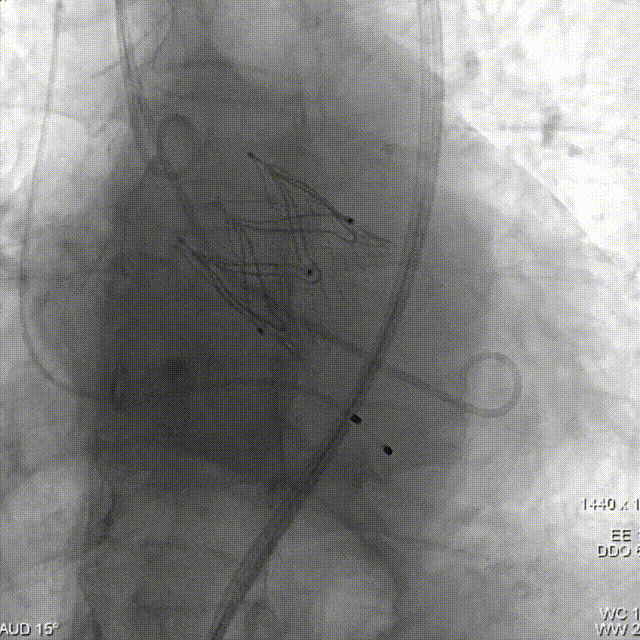

术中影像

THV释放

最终造影